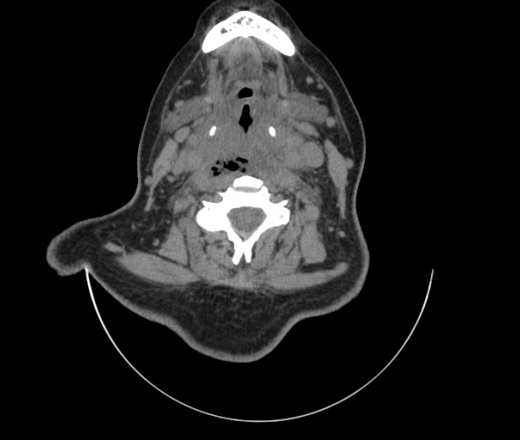

Женщина поступила в х/о спустя 4 дня после того как при употреблении карася подавилась костью.

Наличие газа в средостении на протяжении тел С2-С6 (медиастинальна эмфизема); рыбная кость на уровне тела С6.

Эвакуировали почти 100мл гноя. Но кость не смогли найти. Думаю что она даст дальнейшее ослоднение. Эндоскопически за черпалонадгортаной звязкой не смогли зайти в пищевод, все мягкие ткани отечные, просвет пищевода сдавлен. По всей видимости параэзофагеальная клетчака тоже задействована. Эмпиема, если ее можно так назвать, незнаю как правильно дошла до уровня яремной вырезки. Чем закончиться напишу. Ждем медиастинита.

Флегмона заглоточного пространства шеи, только операция, флегмоны вскрывают. Риск медиастинита.

Согласен с Вами; конечно, наличие газа в клетчатке ретрофарингеального пространства (затмение с опечаткой..). К сожалению, процесс "продвигается" к медиастиниту. Но почему никто, не отмечает наличие рыб. кости; или это для Всех очевидно?